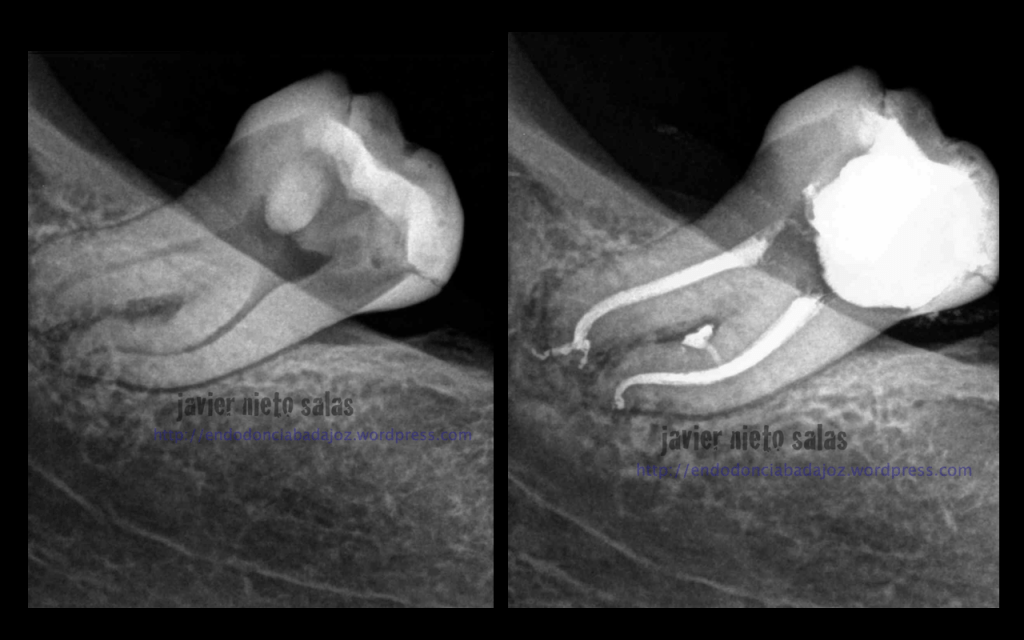

Después de unos 9 meses, la paciente nos llegó a revisión, la lesión ha regenerado correctamente, éxito en el tratamiento: